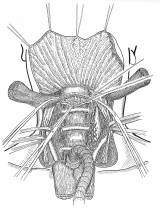

器械吻合器を用いた、咽頭部食道癌摘出後再建法

首の解剖の本と首っ引きで描きました。